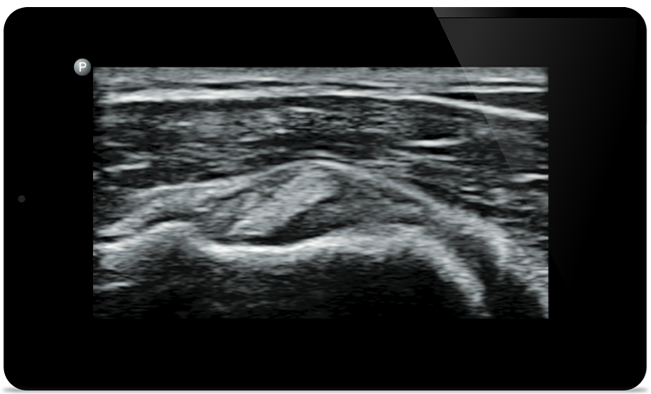

Padstatic case example image

See more when it counts

From revealing the subtle details of an image to uncovering enriched tissue definition from multiple angles, Lumify can help you make real-time decisions with more confidence from assessment through recovery.